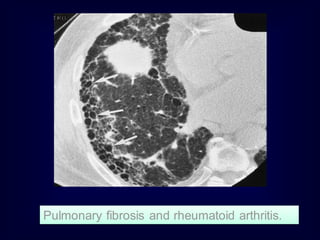

Pulmonary fibrosis and rheumatoid arthritis.